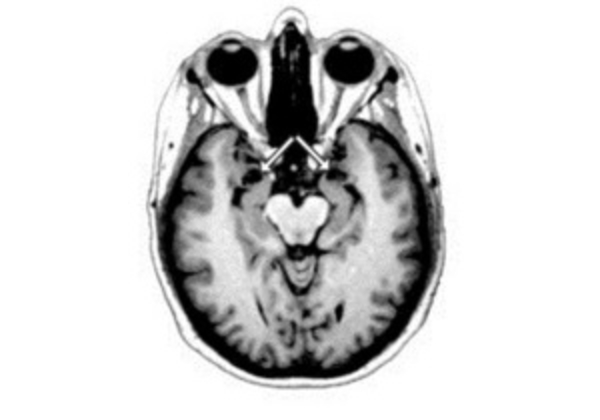

Авторы исследовали ткани головного мозга, полученные после вскрытия 59 женщин, умерших в возрасте от 32 до 101 года. Мужской микрохимеризм, то есть присутствие клеток плода мужского пола в организме матери, был выявлен в 63 процентах случаев. ДНК зародыша мужского рода обнаруживали во многих участках головного мозга, где, как предполагается, они присутствовали все время, прошедшее после беременности. Самой старой носительницей ДНК своего сына в головном мозге была женщина, умершая в возрасте 94 лет.

26 женщин не имели никаких неврологических заболеваний, у 33 была болезнь Альцгеймера. В головном мозге последних наблюдалось незначительное превышение количества микрохимерической мужской ДНК.

Авторы отмечают, что небольшое количество обследованных субъектов и неизвестная история беременности этих женщин не позволяют говорить о какой бы то ни было связи между болезнью Альцгеймера и количеством мужской ДНК фетального происхождения в тканях мозга.

Опубликованное исследование также не выявило корреляций между мужским микрохимеризмом в головном мозге женщин и состоянием их здоровья. Однако в других исследованиях Центра Хатчинсона было обнаружено, что присутствие фетальной мужской ДНК в организме женщин может оказывать влияние на развитие некоторых видов рака и аутоиммунных заболеваний.